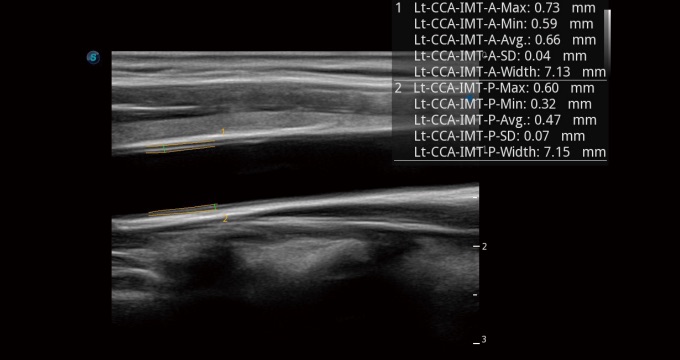

血管內(nèi)中膜的厚度值是預(yù)測心血管疾病風(fēng)險(xiǎn)的重要指標(biāo),Auto IMT可以實(shí)現(xiàn)血管近場和遠(yuǎn)場內(nèi)中膜厚度的自動(dòng)測量,為臨床提供快捷有效的診斷工具。